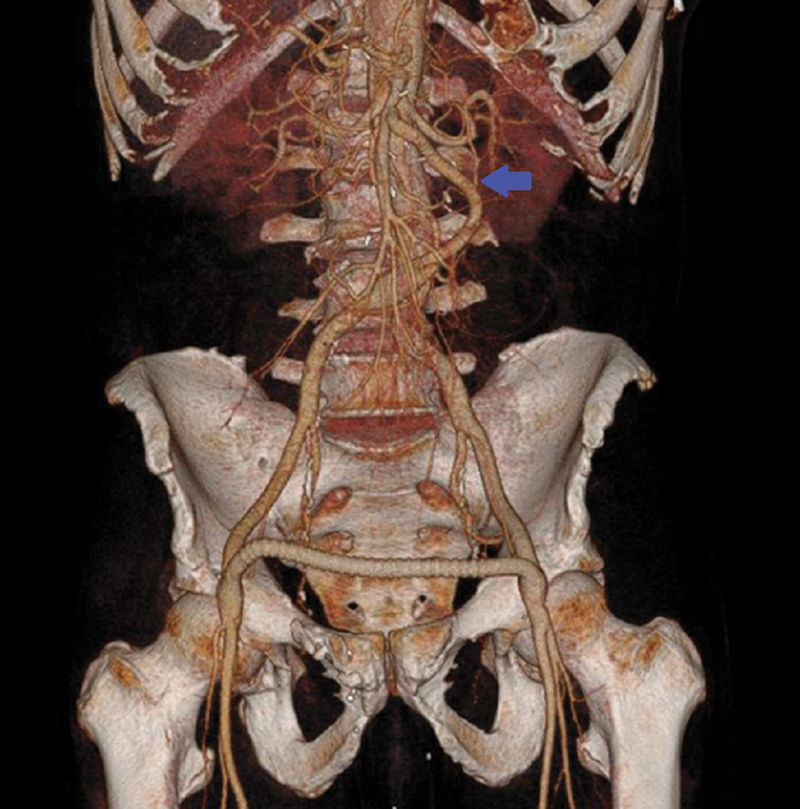

A 57-year-old male patient who underwent an open hemiarch repair with a femoral-femoral crossover bypass and right lower extremity fasciotomies for an acute Type A aortic dissection with limb ischemia presented 5 weeks' postrepair with a 20-pound weight loss due to intermittent hemodynamic collapse of the dissection flap over the origin of the superior mesenteric artery. This case highlights the challenges a dissection flap can cause after an urgent Type A aortic dissection repair.